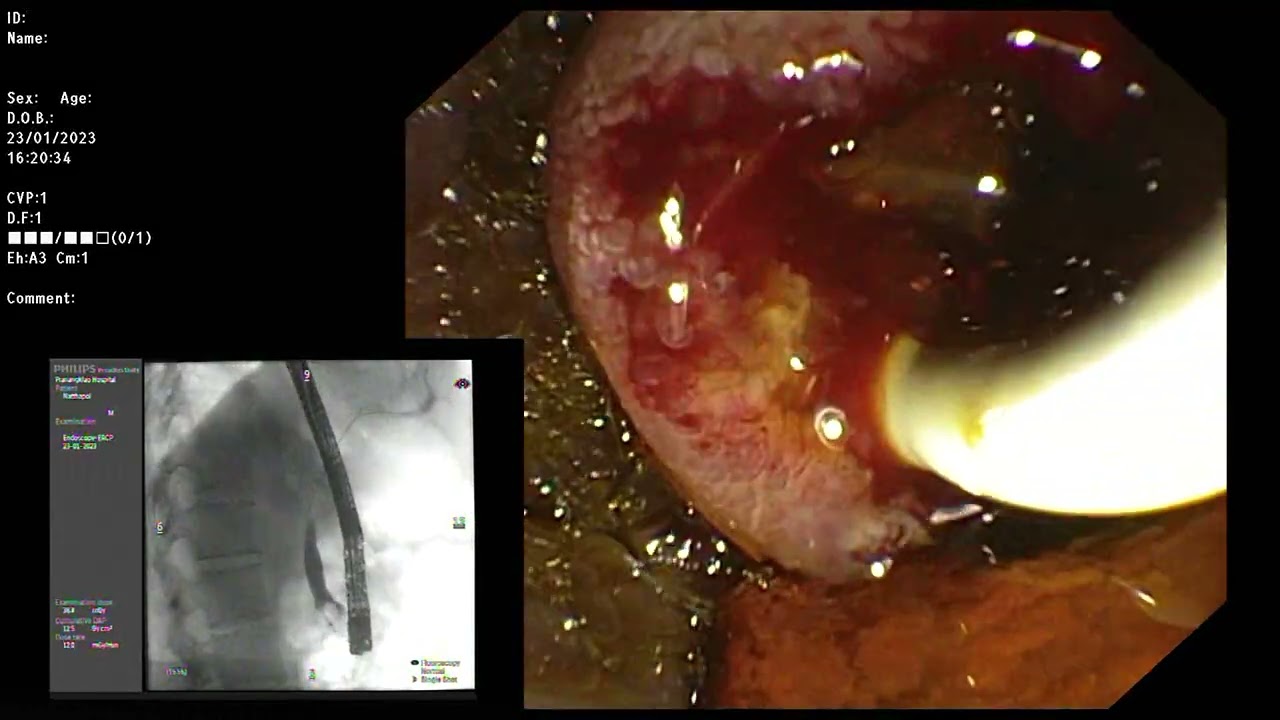

ERCP ; CBD cannulation of intradiverticular type ampulla.